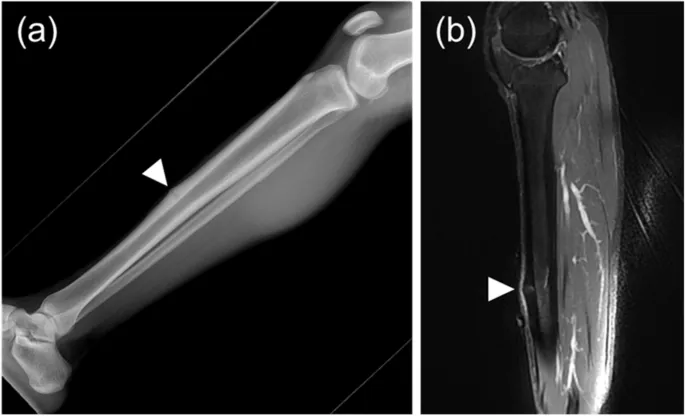

- Stress Fx Imaging: X-ray late; MRI early (edema).

- Common Sites: Tibia, metatarsals (March #), navicular (high-risk).

- Shin Splints (MTSS): Tibial periostitis.

⭐ MRI is the most sensitive imaging modality for the early detection of stress fractures, revealing bone marrow edema often before X-rays become positive.

- Stress fractures: MRI (marrow edema) or bone scan for early diagnosis before X-ray.